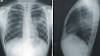

What is 'white lung' pneumonia, and why is it reportedly on the rise in kids? What parents need to know In this picture taken on Nov. 7, A doctor examines the X-ray of child with breathing difficulties at the emergency ward of the government-run Chacha Nehru Bal Chikitsalaya children hospital in New Delhi.